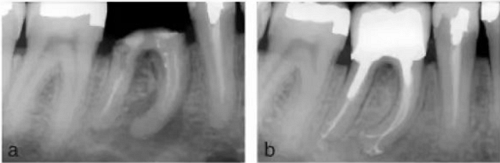

在白種人中,下頜第一磨牙主要為雙根—近中根和遠(yuǎn)中根,但其中根管形態(tài)各異。根據(jù)Vertucci 的分類,下頜第一磨牙中 59%的近中根在根尖處為獨立的雙根管,28%為兩根管融合成單根管單根尖孔,12%為單根管,1%為三根管(8,9)(圖 11a,b)。在另一項研究中,下頜磨牙的近中中根管(MM)發(fā)生率在 1%至 7%之間變化(92-99)。三個近中根管可以是獨立的(92-95)或融合稱為兩個根管,在根尖有兩個根管口(96-99)。

在歐洲人中,下頜第一磨牙的遠(yuǎn)中根大約 70%為單根管。15%為雙根管融合為單根管,5%為兩個獨立的根管,8% 為單根管分為雙根管,2%為單根管分為雙根管并再次于根尖1/3融合為單根管(8)(圖12a-b)。